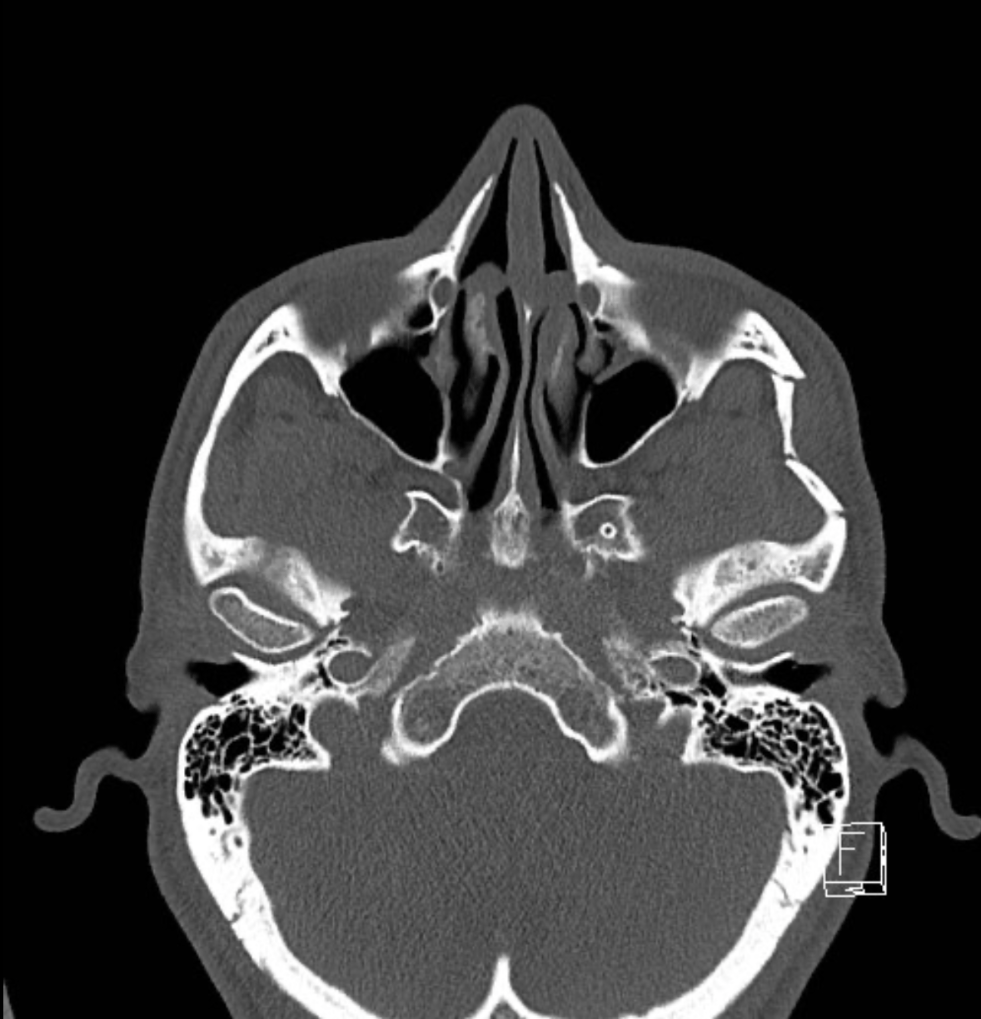

While attempting to demonstrate how close one can get to a horse without spooking it, a patient takes a hoof to the side of the face, resulting in a depressed facial fracture. Which two bones form the damaged structure shown?

Answer: Zygomatic and temporal bones

These bones form the zygomatic arch. The frontal bone does not contribute to the zygomatic arch and is less likely to be fractured in blunt force trauma to this area of the face, and is not affected in the axial CT image shown.